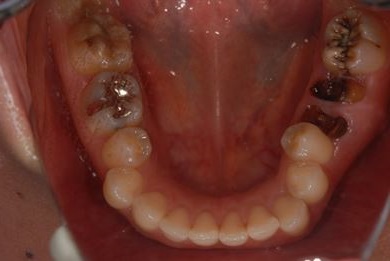

セラミック治療+骨造成(欠損部)

| 性別/年齢 | 女性 / 34歳 | ||||||||||||||||||||||||||||||||

| 主訴 | 前歯と奥歯の虫歯と、前歯の歯並び(でこぼこ)・歯の形(小さくとがった形が気になる)を治したい。 | ||||||||||||||||||||||||||||||||

| 治療方針 | 上顎前歯1歯抜歯し、オールセラミックブリッジ、クラウン、ラミネートベニアにて審美的回復を行う。 | ||||||||||||||||||||||||||||||||

| 治療内容 | オールセラミッククラウン2本、ジルコニアフレームオールセラミックブリッジ3本、オールセラミックラミネートベニア2本、骨造成(欠損部) | ||||||||||||||||||||||||||||||||